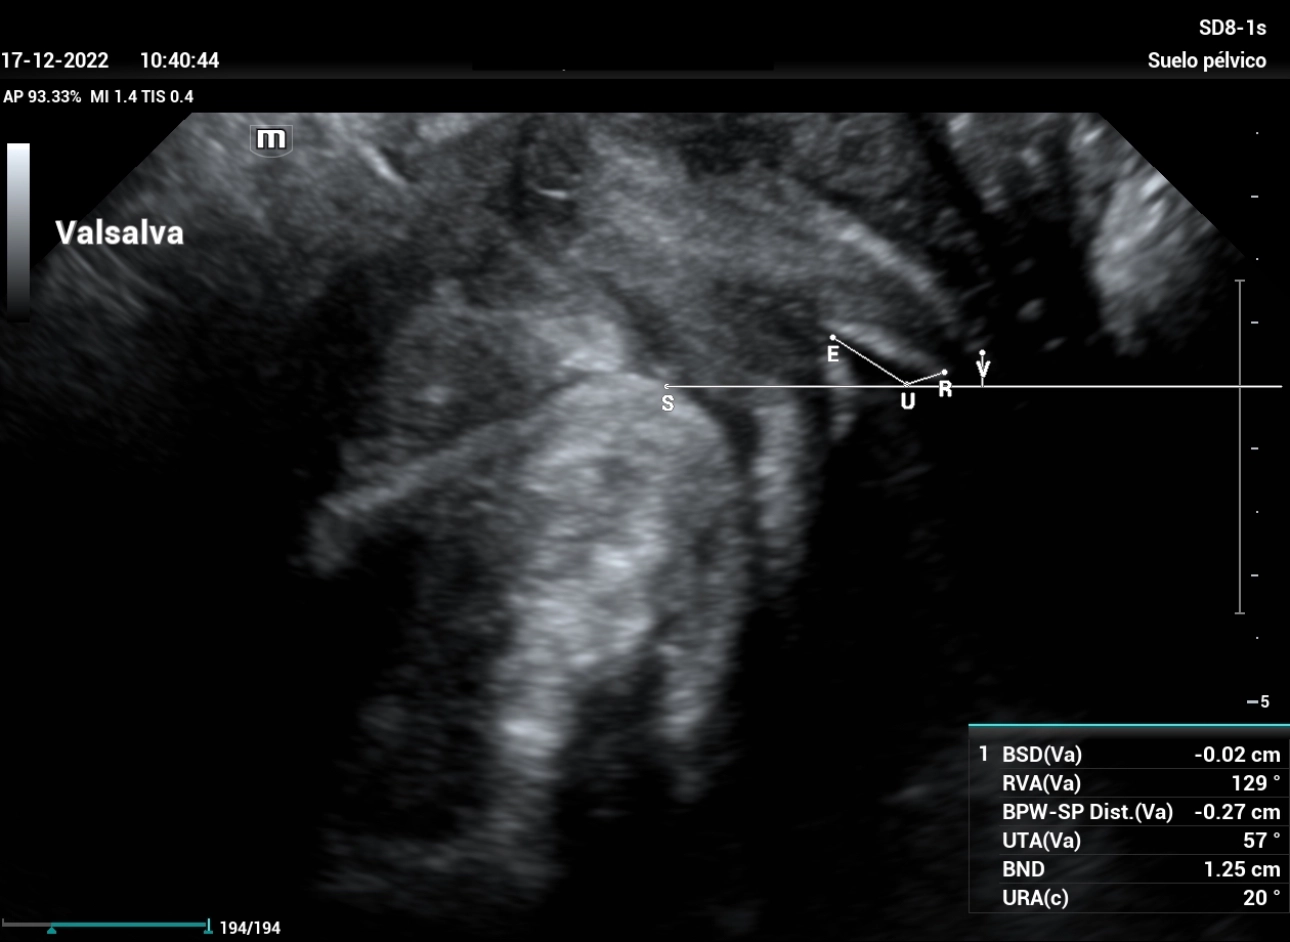

stress-urine-fig7

Figure 7: Performing Valsalva maneuver, we can observe a Bladder Neck Descent within mild cystocele, funneling of the bladder neck, with angles that do not represent a significant change.